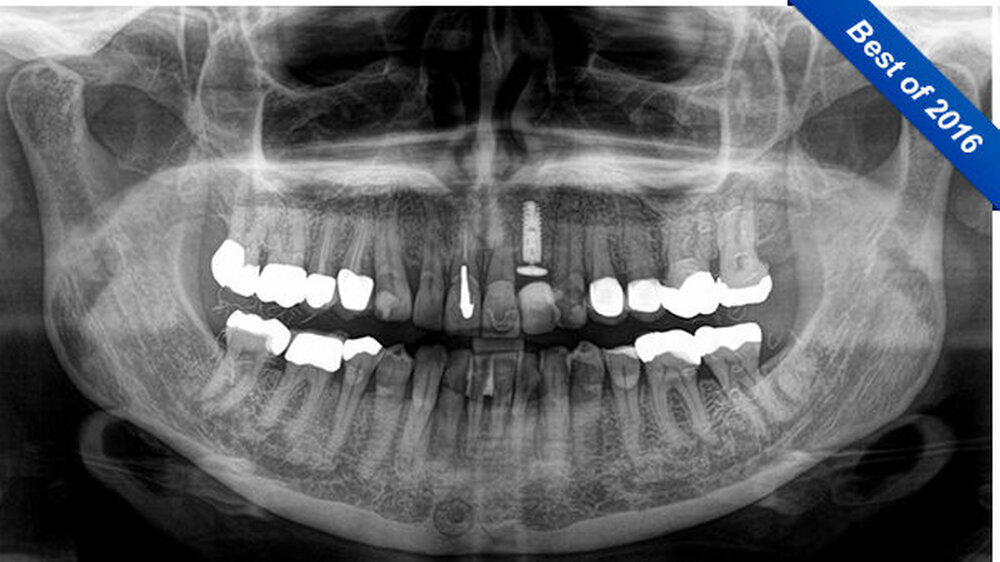

Im April 2016 stellte sich eine 58-jährige Patientin zur Kontrolluntersuchung in unserer Praxis vor. Die Anamnese war unauffällig. Es wurde ein OPG (Sirona, Orthophos SL) zu einer Implantatversorgung an Regio 22 gefertigt (Abbildung 1).

Auf der Röntgenaufnahme waren im Seitenzahngebiet der Patientin unklare, diffuse, faden-ähnliche Verschattungen sichtbar, die wie kleine Fusseln aussahen. Da das Röntgengerät kaum ein Jahr alt war, ging der behandelnde Zahnarzt von einer falschen Einstellung beziehungsweise Fehlaufnahme aus.